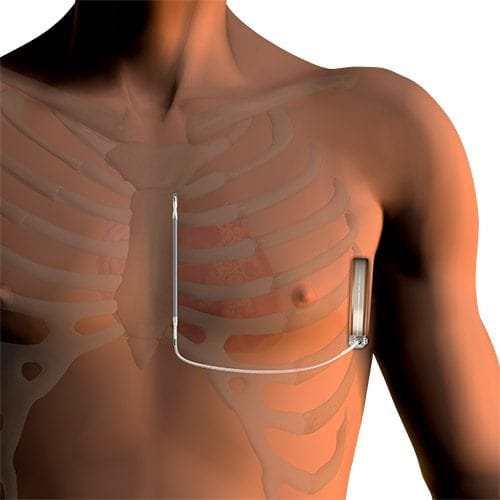

The EMBLEM S-ICD System is the first and only FDA approved product with both the device and the leads inserted beneath the skin, with no leads inserted through any veins, and thus with no leads placed inside or even touching the heart at all. “This leaves the heart and blood vessels untouched and so provides a safer alternative to conventional implantable defibrillators without the complications associated with cardiac wires,” explains Dr Gopal.

The Subcutaneous Implantable Cardioverter Defibrillator shock device is 83.1mm wide, 69,1mm high and 12.77mm thick and weighs 130 gram and is implanted in a space between two muscles on the left side of the patient’s body.

Step 3: The device is placed in a space between two muscles in the left flank (the Latissimus dorsi muscle and the Serratus anterior muscle).

Step 4: A tunnel is created underneath the skin adjacent to the sternum (breast bone).

Step 5: The shock lead is positioned to run firstly from the device underneath the skin, to the bottom of the sternum – thus from the left side of the thorax to the centre of the thorax.

Step 6: Then the lead is pulled upwards through the tunnel under the skin. The second half of the lead makes a 90 degree turn and runs straight upwards adjacent to the sternum, but below the skin.